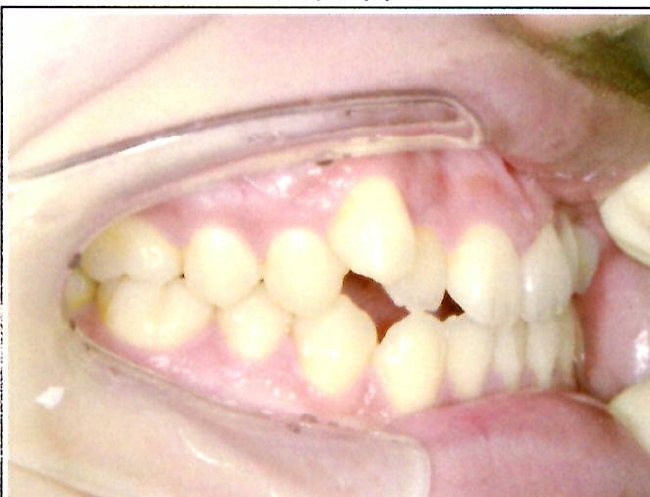

| 主訴・治療前の状態 | 前歯が噛み合っていない状態(開咬傾向)で、犬歯がやや前方に突出しており、見た目にお悩みがありました。 |

| 治療内容 | 上下左右の第一小臼歯(4番)計4本を抜歯し、そのスペースを利用して歯列を整え、前歯の噛み合わせを改善しました。 |

| 治療結果 | 前歯がしっかり噛み合うようになり、見た目も美しく整いました。患者様の満足度が非常に高かった症例です。 |